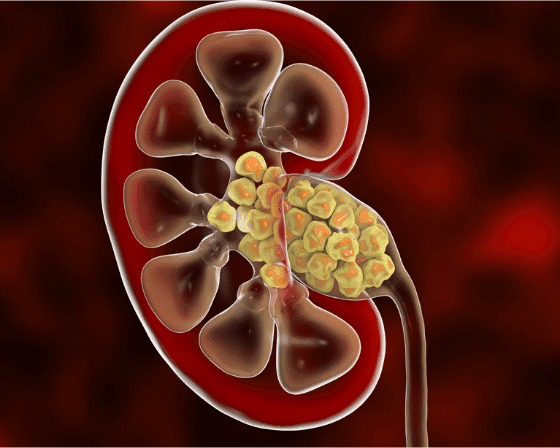

Kidney stones are hardened salt and mineral deposits inside the kidney. Other names include renal calculi, urolithiasis, or nephrolithiasis. The stones can originate anywhere in the urinary tract, i.e., the bladder or the kidney. Common causes include particular medical conditions, obesity, certain dietary choices, and usage of some medications and supplements. The urine concentration in one area results in crystallization and accumulation of minerals into stones.

Other natural stone-forming chemicals include cystine, phosphate, oxalate, and xanthine. The average size of these stones is six or lower millimeters, and the common types of kidney stones include uric acid, calcium, cystine, and struvite. After completing their development, the stones transfer to the ureter via the urinary tract or remain in the kidney.